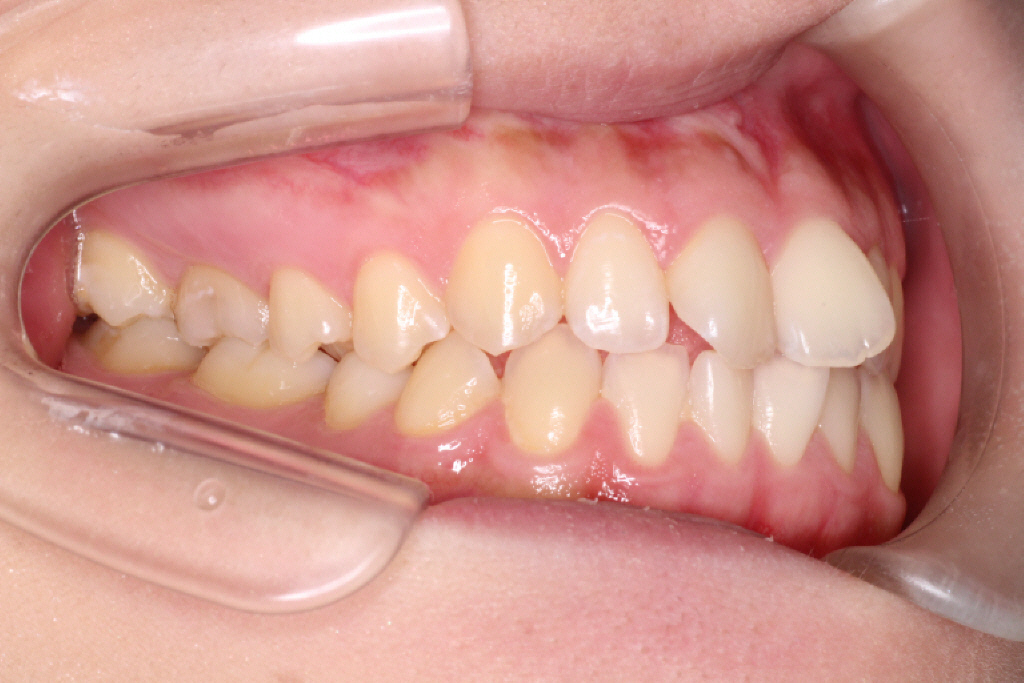

初診時の状態です。

初診時の奥歯の噛み合わせは上の歯と下の歯が1歯対1歯で噛めているので、奥歯はそのまま動かさず、

ねじれている前歯を動かしていきたいのですが、スペースがないので、そのスペースをつくらなければなりません。

左側が私の歯列です。

右側の歯列と比べてみると広いのがわかります。

歯のアーチが狭いわけではないので拡大には限界があります。